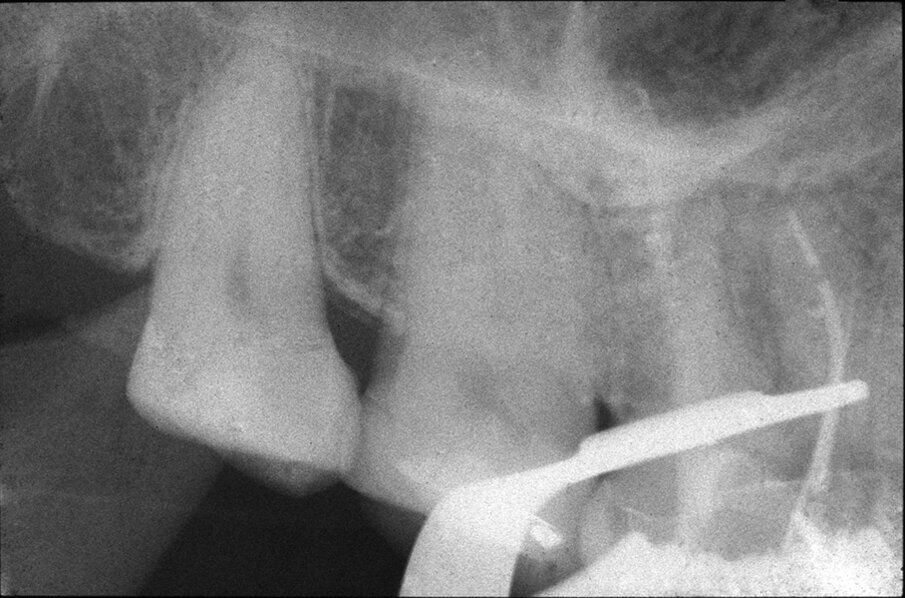

Le perforazioni del terzo medio avvengono nella maggior parte dei casi durante la preparazione della cavità d’accesso o, più spesso, durante le fasi di detersione e sagomatura o infine durante la preparazione dello spazio per un perno con l’utilizzo di frese tipo Largo, Peeso, Gates Glidden o simili (Figg. 2a-2f).